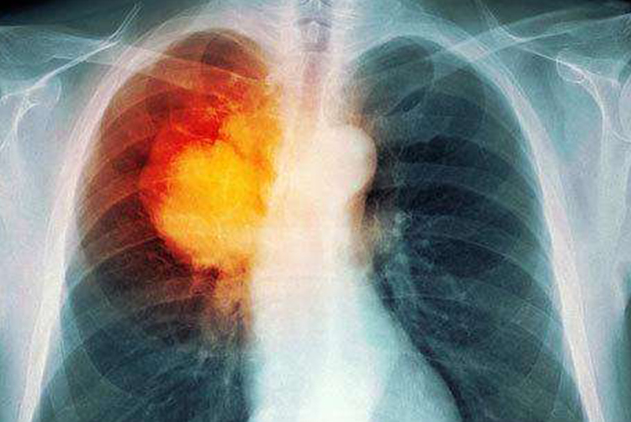

很多人如果对自身身体情况的改变不是很关注的话,那么即便已经是肺癌晚期了,依然没有察觉到。为了避免出现这种乌龙事件,也为了让大家的身体健康能够得到重视,下面就来为大家盘点一下肺癌晚期症状都有哪些,如果你的身上出现了下述中盘点的症状那么就要注意了,抓紧时间到身边到医院做系统检查,看看是不是真的是肺癌晚期。如果是乌龙事件那肯定是皆大欢喜,但如果真的是肺癌晚期的话,就要抓紧时间接受治疗了,毕竟早一点治疗的话,对自己的身体也会有更多的帮助,适当也会延长一下自己的寿命。

肺癌如果进入到晚期阶段的话,不仅会频繁的咳嗽,而且少部分的时候还会直接咳血出来。如果患者经常性咳嗽并且咳血的话,就要抓紧时间去治疗了。因为这种咳血的症状可不是什么毛细血管破裂或者是胃部不适了。而且基本上出现咳血症状的话,不是肺癌晚期也已经是中期阶段了,所以要从思想上重视起来。

不知道大家发现了没有,几乎所有的肺癌晚期患者到了这个阶段,身形都会有明显的消瘦,不仅看起来非常的单薄,而且也会有一种无力感。所以如果你没有接受系统的治疗,甚至都没有发现自己患病,但是近期身体有明显消瘦,而且饮食上也没有明显的减少,那么不管是不是肺癌晚期,起码在身体健康上肯定是出现了其他方面的问题,所以也需要在尽快去接受治疗,这样才是对自己身体健康负责的一种表现。

部分肺癌晚期症状会有头晕恶心等现象,不过这种现象也不是所有的肺癌患者身上都会出现,更多的还是因为到了肺癌晚期阶段后,癌症患者的癌细胞会转移,如果转移到颅内的话,那么肯定也就会出现头晕恶心等肺癌晚期症状了。但如果是转移到腹部的话,则会出现腹痛腹胀或者是腹下水等现象,还有这些症状在处理起来都很困难。而且腹痛腹胀也不是只有一两次,因此千万不要当成是普通的腹部不适或者是胃部不适来治疗,也不要自己买药来缓解疼痛,必须到医院接受医生的检查,然后根据自己身体的不同情况,让医生制定相关的治疗以及解决方案,这样才是对自己负责任的一种表现。

好了,以上就是关于肺癌晚期患者会出现的症状总结和盘点了。对于患者来说,一旦自己的身体出现了上述中盘点的现象,那么就要积极的去治疗和配合。还有就是,为了防止出现患者已经进入到肺癌晚期阶段还没有发现病症的现象,不管身体健康怎么样,尽量每年都要接受一次体检,这样身体上即便是出现了任何的问题也可以在尽快发现并且治疗,如果是肺癌患者的话,早期阶段治疗的话痊愈的可能性很大。